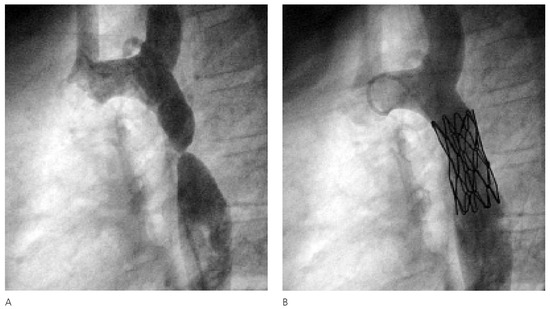

Fallbeschreibung. Ein 10jähriger Knabe wurde zur Abklärung eines Systolikums bei unauffälliger Anamnese und insbesondere uneingeschränkter körperlicher Belastbarkeit vorgestellt [...]